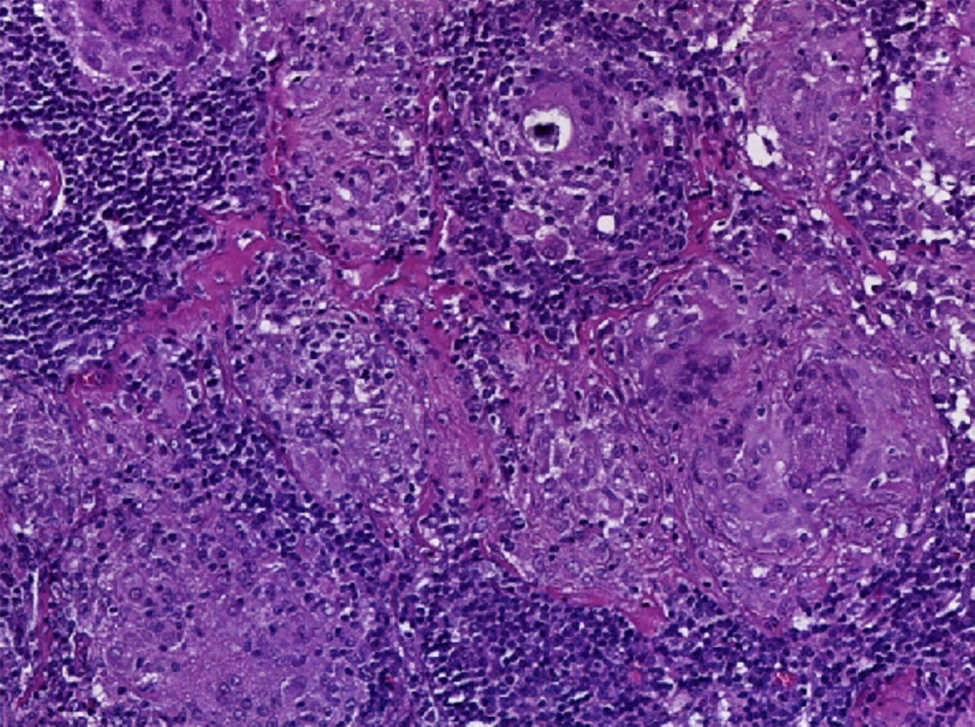

El hallazgo histológico característico de la sarcoidosis es la presencia de granulomas epitelioides no caseificantes esparcidos de manera difusa en diferentes tejidos, pero que principalmente afectan al ganglio linfático.

Los granulomas de la sarcoidosis tienen aspecto compacto, con límites bien definidos. Pueden encontrarse en distintas etapas de evolución, que van desde granulomas altamente celulares hasta lesiones con celularidad disminuida, con fibrosis o con hialinización progresiva; además, no presentan necrosis central ni evidencia de cuerpos extraños, lo cual permite diferenciarlos de los granulomas observados en infecciones por micobacterias, micosis sistémicas e infestaciones por metazoarios.

El granuloma típico de la sarcoidosis presenta dos zonas características que se describen a continuación:

La zona central o folículo, constituida por un denso conglomerado de células epitelioides en forma de racimos, acompañados de linfocitos, macrófagos, células gigantes multinucleadas de Langhans, mastocitos y fibroblastos. En el 60% de los casos se observan estructuras de aspecto estelar (o cuerpos asteroides) y estructuras laminares llamadas cuerpos de Schaumann, de 1-15 μm de diámetro y PAS+. En estudios con métodos inmunohistoquímicos, la zona central de un granuloma activo consiste en macrófagos en diversas etapas de activación y diferenciación. Esta zona está rodeada por células T CD4+ intercaladas con un pequeño número de células T CD8+ y células B.

La zona periférica, formada por un anillo de linfocitos, monocitos y fibroblastos. En la periferia del granuloma se acumulan las células T reguladoras CD3 + /CD4+/CD25+/ +Fox P3, además de células T CD8+ y fibroblastos, que cuando disminuye la actividad de los granulomas, producen la fibrosis.

En la forma crónica de la enfermedad, los granulomas pueden estar encapsulados por un halo fibroso o pueden ser sustituidos por cicatrices de tejido fibroso y hialino32 33 34.

Se realizó la biopsia de ganglio supraclavicular con tinciones de hematoxilina/eosina, Grocott, Ziehl-Neelsen y PAS. Los cortes histológicos mostraron ganglios linfáticos con pérdida de la arquitectura, secundaria a la formación de múltiples granulomas no caseificantes confluentes entre sí (Fig. 7), constituidos por numerosos macrófagos epitelioides, células gigantes tipo Langhans y otras tipo cuerpo extraño. Se observaron, de forma ocasional, calcificaciones concéntricas o cuerpos de Schaumann (Fig. 8) y formas compatibles con cuerpos asteroideos (Fig. 9). Con las tinciones especiales no se observaron microorganismos, y las pruebas de PCR así como los cultivos en tejido del ganglio para Mycobacterium tuberculosis fueron negativos. Diagnóstico histopatológico: ganglios linfáticos supraclaviculares con linfadenitis crónica granulomatosa no caseificante concordante con sarcoidosis.

El diagnóstico de sarcoidosis se sospechó ante la presencia de un padecimiento sistémico con hipercalcemia, hipercalciuria y litiasis urinaria, acompañadas de elevación de los niveles de la ECA y del sIL-2R. Se comprobó, mediante el estudio histopatológico de la biopsia de ganglio linfático, la presencia de múltiples granulomas no caseificantes conformados por macrófagos epitelioides, células gigantes tipo Langhans, y la presencia de cuerpos de Schaumann y cuerpos asteroideos. Sin embargo, a su ingreso, no se pudo realizar el análisis citológico del lavado broncoalveolar ni se pudo aplicar la prueba de Kveim-Siltzbach.